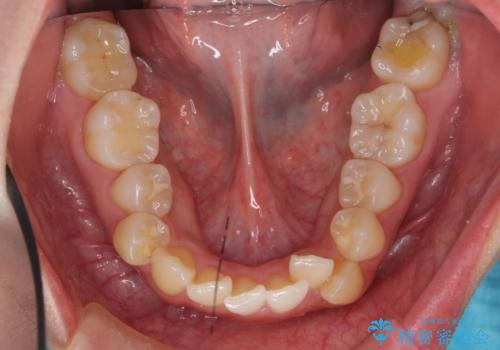

- 前歯のがたつきと正中のずれを主訴に来院。

小臼歯を4本抜歯しています。

歯を抜いたことで、口元が下がって、横顔も理想的なラインになりました。